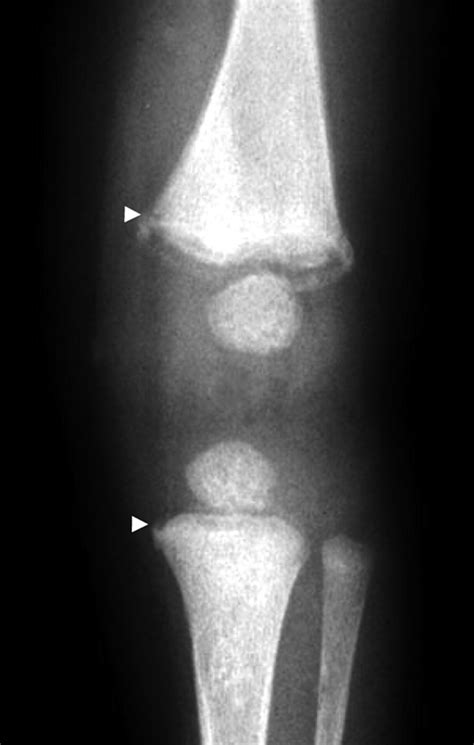

A Bucket Handle Fracture is a specific type of fracture where a segment of bone is displaced, often in a manner that resembles the handle of a bucket. This type of fracture is commonly seen in the knee, particularly in the medial meniscus, but can also occur in other joints. The fracture typically involves a longitudinal split in the bone, with the displaced segment often remaining attached to the surrounding ligaments or tendons.

• Imaging Tests: X-rays, MRI, or CT scans to visualize the fracture and determine the extent of the damage.

Imaging tests are crucial for confirming the diagnosis and planning the appropriate treatment. X-rays can show the fracture line, while MRI and CT scans provide detailed images of the soft tissues and bone structure.